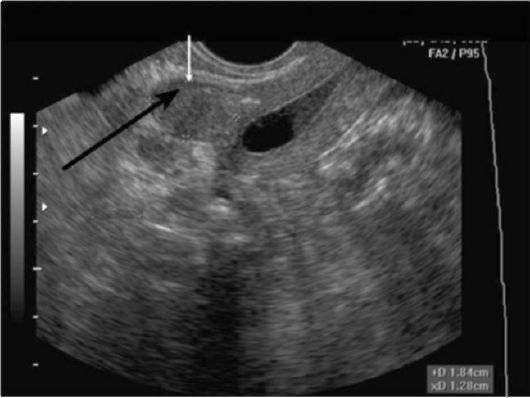

Для диагностики состояния используются следующие методы:

- УЗИ – наиболее популярный метод;

4. Регулярные медицинские осмотры. Важно проходить регулярные гинекологические осмотры, особенно если у вас есть предрасположенность к заболеваниям репродуктивной системы. Это позволит своевременно выявить возможные изменения в состоянии матки и других органов. Ультразвуковое исследование органов малого таза может помочь в ранней диагностике миомы и других заболеваний.